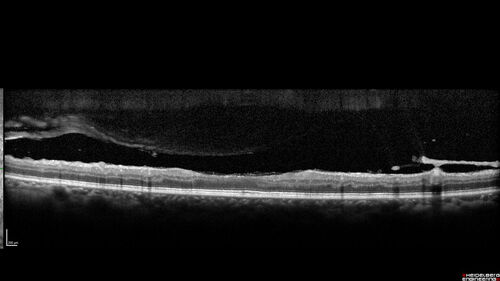

Severe Proliferative Diabetic Retinopathy and Good Vision

49 year old man with vision loss in the right eye for 2 weeks. VA 20/40 OD, 20/63 OS. DM x 15 years and HTN.